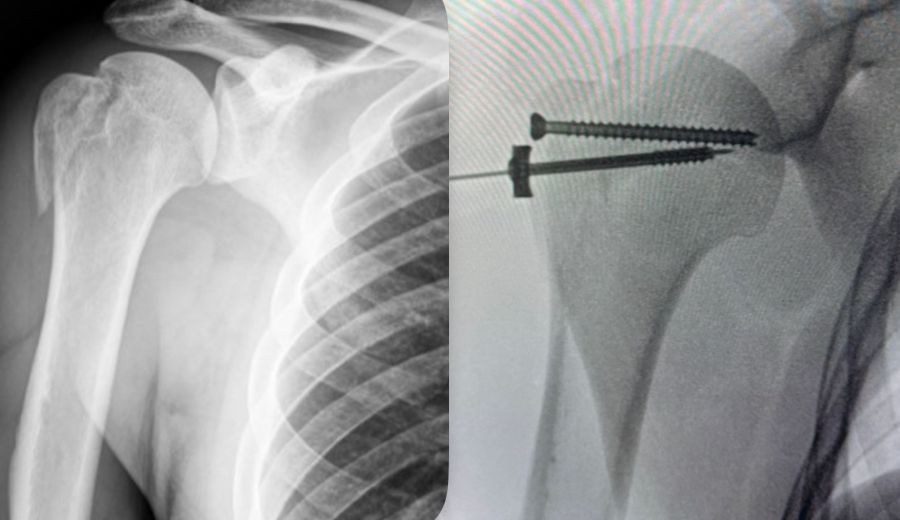

Fotos y videos

• Atención a fracturas

Ortopedista Desgaste articular-Fracturas-Lesiones deportivas